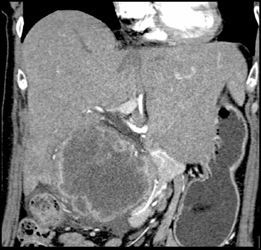

Gallbladder Cancer